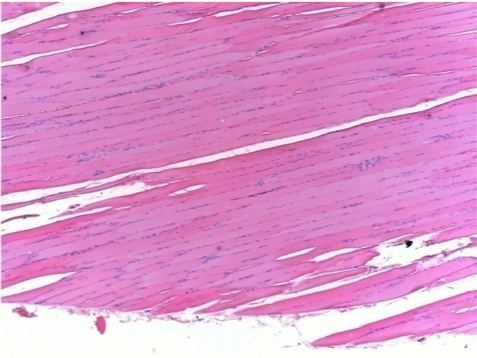

L:Pretibial-No treatment